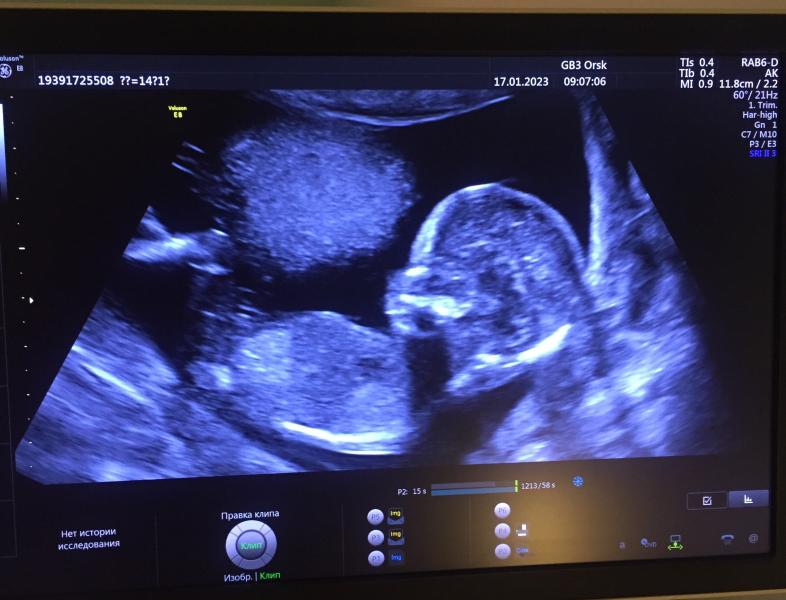

На 7 неделе (по узи) славала кровь на определение плода, пришел ответ мальчик, сегодня на 3 минутном скрининге узистка сказала предворительно девочка, а я прям там мальчика вижу🤣

Вроде еще не сформированы половые органы и смотрят по наклону бугорков,но если это опустить,то я тоже вижу мальчика с причиндалами 😁

Половые органы сформированы окончательно к 16 неделям.